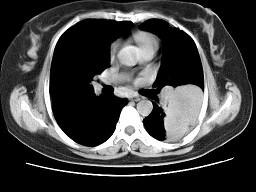

问题 女,52岁,左侧背痛一月,胸部CT如图,最可能的诊断为 ( )

选项 A、左肺炎性假瘤 B、肺隔离征 C、左肺周围型肺癌 D、左肺感染 E、左肺中央型肺癌

答案 A